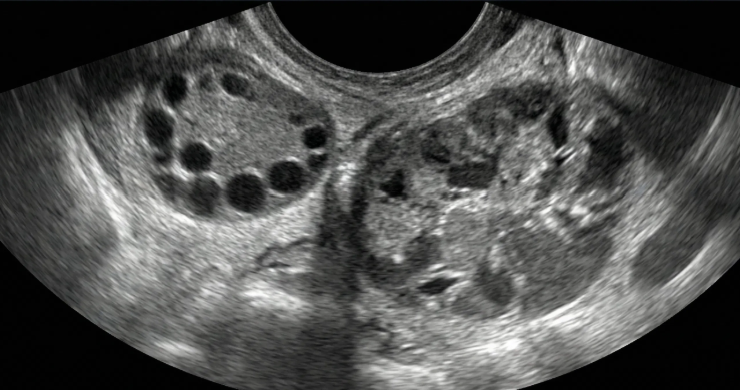

Gestação ectópica (US)

Ferramenta educacional baseada no NICE guideline NG126 (2019, atualização 2023), com abordagem conservadora. Ajuda a reconhecer sinais ultrassonográficos de gestação ectópica tubária e a lembrar a necessidade de correlação clínica e laboratorial.

Indica ectópica tubária (USTV)

Alta probabilidade (USTV)

Possível ectópica (USTV)